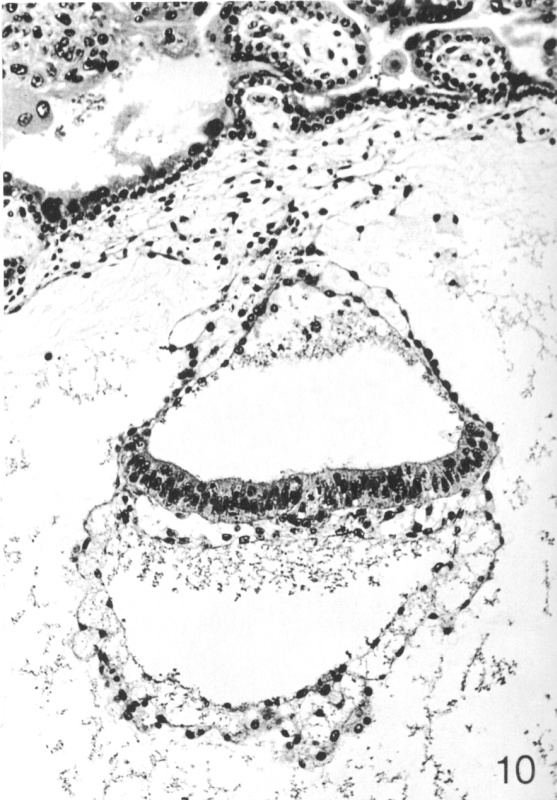

IntroductionStage 7 embryos are in the presomite period with a well-defined embryonic disc. They have an estimated postfertilization age of approximately 18 to 21 days and a greatest length of 0.6 mm. The embryonic disc is symmetrical and slightly convex in the plane of its longitudinal axis. The gastrulation (primitive) node and notochordal process can be identified. Read more... |

Section 36(View All Sections) |

Section 44-2-2More Figures... |